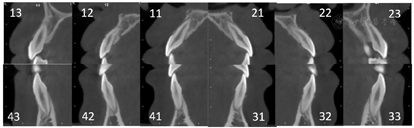

CBCT牙齿截图显示:上下前牙未见明显牙根吸收,上下前牙牙根位于骨松质内(图7)。关节截面显示:TIPA治疗后髁突表面发生功能性改建;髁突位置发生后退,关节窝随之发生相应改建。Ⅱ期治疗后髁突位置稳定,关节间隙恢复正常(图8,图9,图10)。治疗前、中、后头影测量结果见表1,矫治器前后头影描绘重叠图见图11。

2.TIPA是一种新型的功能矫治器[3],主要结构是双侧后牙合垫区由前下后上的两长斜导面组成,利用咀嚼力"渐进式"逐渐诱导下颌骨(骨、牙槽骨、牙)向后运动、上颌骨(骨、牙槽骨、牙)向前运动以及诱导髁突、关节窝发生生理性改建(图9、图10)。相较于头帽-颏兜(Facemask,FM)、Frankel Ⅲ(FR Ⅲ)、反式Twin Block(RTB)、双阻板磁力矫治器、骨性支抗弹性牵引等传统早期矫治装置,其主要针对于以下颌发育过度为主的骨性Ⅲ类生长期错合畸形,独有的长斜面结构有利于咀嚼、前伸和侧方运动,力更接近生理性,患者易适应和配合,且不要求后退下颌重建上下颌位关系,制作简单。术后患者矫治效果良好,锥形束CT重叠观察到髁突及关节后区发生生理性改建(图10),这与笔者团队的之前TIPA能持续性引起关节区不同区域的不同改建的研究一致[4,5,6]。